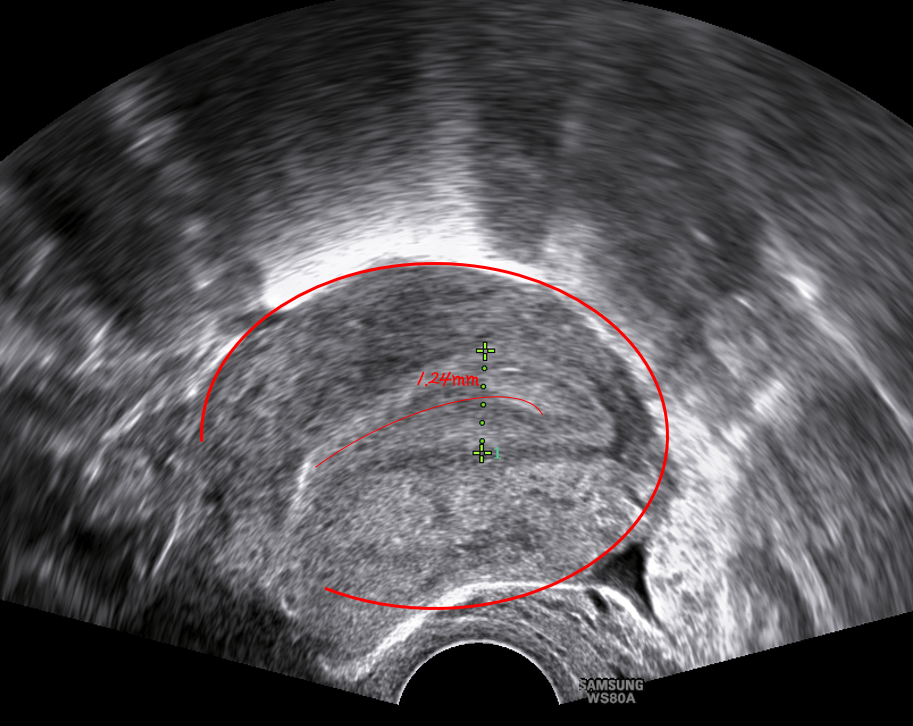

자궁내막은 여성 호르몬의 분비 변화에 따라 한 달주기로 두께가 변화하면서 임신에 대한 준비를 한다. 자궁내막은 난자와 정자가 만나 수정된 배아의 착상이 최종적으로 이루어지는 공간으로 임신에 있어 중요한 역할을 한다. 자궁내막의 두께가 얇을 경우 착상이 진행되지 않아 임신 실패로 어이질 가능성이 크다. 난소에서 난자가 배란된 후 10일 전후의 기간동안 자궁 내막이 가장 두꺼워져 수정란이 착상하기 좋은 상태가 된다. 최소 7mm 는 되어야 하고 평균적으로 8~10mm의 두께가 임신하기 가장 좋은 내막의 두께라 할 수 있다. 자궁내막의 두께가 6mm 이하일 때 임신성공률이 낮아진다.

| 내막 두께 | 임신률 |

| < 6mm | 3.7% |

| 6~8mm | 14.8% |

| 8~10mm | 55.5% |

| 10~12mm | 35.3% |

| 12~14mm | 3.7% |

| >14mm | 0% |